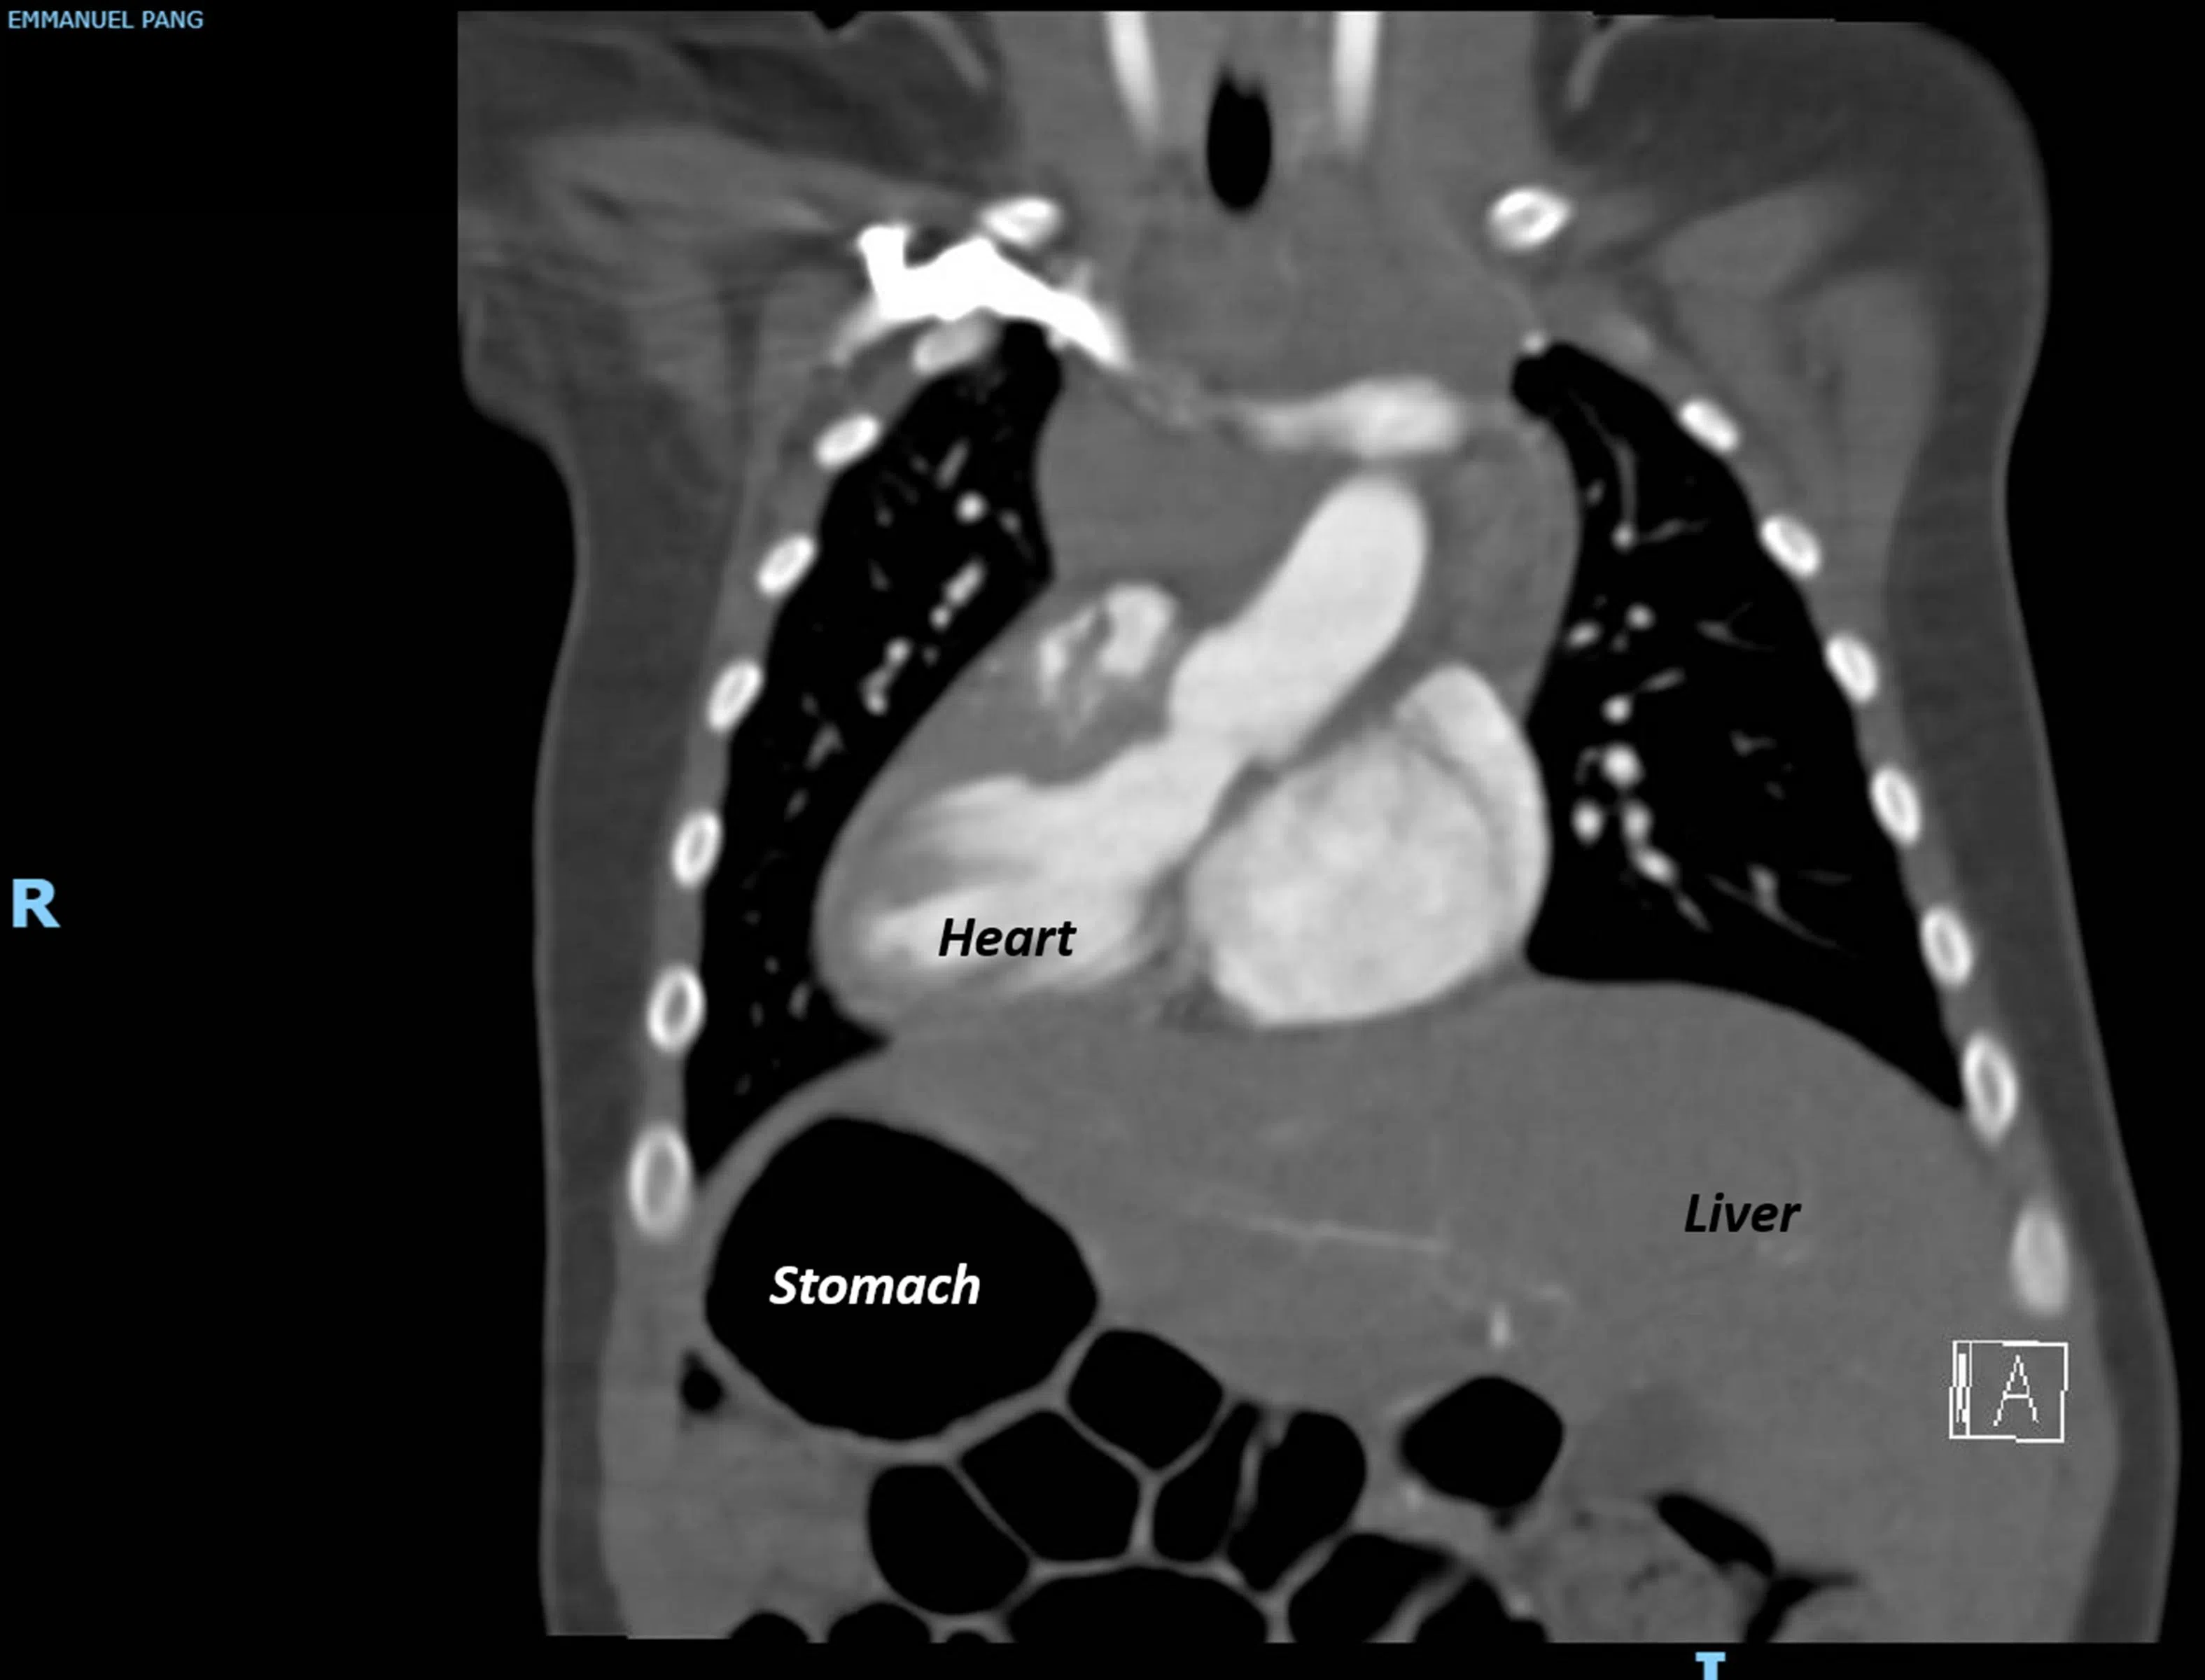

After multiple checks, the baby was diagnosed with situs inversus totalis, a rare genetic abnormality where organs in the chest and abdomen develop in mirror-image positions of normal humans.

While situs inversus totalis alone has no medical disadvantage, the disorder can complicate certain invasive medical procedures.

Dr Chen said: “Usually, the heart is pointing towards the left, but with Emmanuel’s organs being mirror-image, everything was flipped, which is out of the convention for a surgeon.”